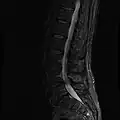

MRI lumbar spine with degeneration (sagittal FAST STIR) -